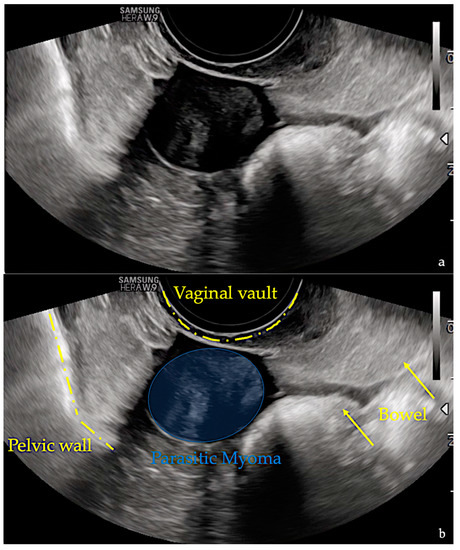

2. Case Report